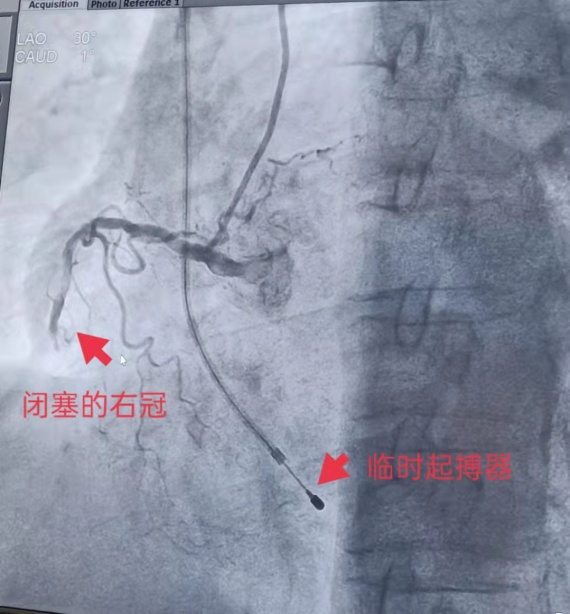

情况紧急,值班医生立即给予双联抗血小板药物口服,征得患者及家属同意后,心内科介入团队在科主任刘世平主任医师带领下立即为患者开通了绿色通道,直接送到介入中心进行急诊经皮冠状动脉介入术。此时,患者心动过缓,必须在植入临时起搏器保护后才能进行冠脉造影检查。

术中冠脉造影显示:冠状动脉三支都已经发生了病变(前降支、回旋支严重狭窄,右冠中段完全闭塞,结合心电图考虑右冠为罪犯血管)。 通过冠脉造影,心内科介入团队准确快速的找到了患者这次发病的罪犯血管—右冠状动脉。 时间就是生命!必须立即打开生命通道! 刘世平主任将导丝顺利通过右冠中段闭塞病变至远端,右冠前向血流恢复,中段存在严重狭窄及血栓影,在给予球囊扩张、血栓抽吸处理后狭窄明显减轻,远端血流恢复正常。 此时患者血压下降,心电监护示起搏心律,经升压、扩容、加强抗血小板等处理后,患者胸痛症状缓解,生命体征逐渐稳定。 术后,躺在病床上的周奶奶感叹道“刚感觉在‘鬼门关’走了趟,幸好人民医院有这项‘好’技术。” 急性心肌梗死急诊介入手术现在可以在津市市人民医院一站式完成,近二个月来,我院心内科介入团队在科主任刘世平主任医师的带领下已独立成功开展了多例冠状动脉支架植入术,随着我院心内科介入诊疗新技术的不断发展壮大,给津市人民群众的健康带来了更方便的保障。 雄关漫道真如铁,而今迈步从头越。心内科团队将继续保持团结向上、锐意进取的良好状态,以一流过硬的医疗技术和优质服务,为广大人民群众的健康保驾护航,为“健康中国”助力!